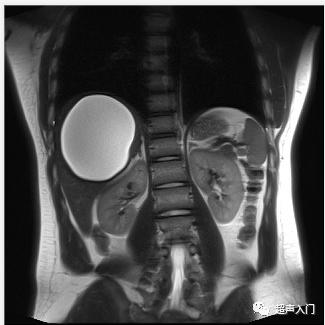

2、腹部增强CT和MRI:诊断价值很高,能显示囊肿与肝内结构的解剖关系,疑有胆道受累时,可行MRCP检查。